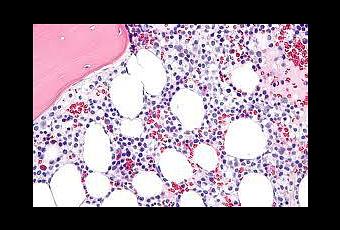

El equipo identificó 95 de estos fosfopéptidos en las superficies de las células malignas tomadas de pacientes con leucemia. Sesenta y uno de los péptidos aparecieron sólo en células cancerosas y no en las normales, informaron los investigadores en Science Translational Medicine .

A continuación, el equipo extrajo las células T de 26 pacientes con leucemia: 14 con leucemia linfocítica crónica y 12 con la leucemia mieloide aguda, una forma más agresiva de la enfermedad. Mientras en los voluntarios sanos todas las células T que reconocieron albergaban fosforopéptidos cancerosos, sólo sucedió lo mismo con cinco pacientes con un tipo de leucemia más suave, al igual que dos pacientes con leucemia mieloide aguda. Los investigadores encontraron que las células T llevaban proteínas que marcaron como “células de memoria”, lo que indica que las células se habían encontrado con los fosfopéptidos -tal vez en las células cancerosas- con anterioridad.